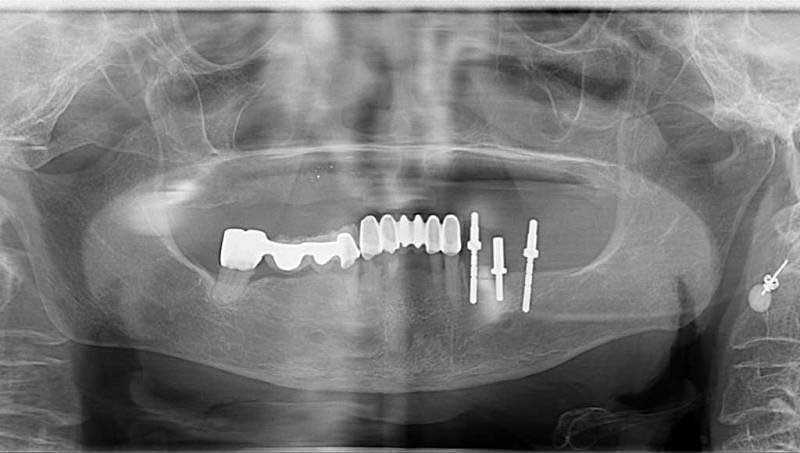

案例3